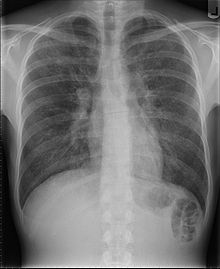

- Pneumocystis-Pneumonie

1981 beschrieb Michael S. Gottlieb in der am 5. Juni erschienenen Ausgabe des Morbidity and Mortality Weekly Report, einem wöchentlichen Bulletin der US-Gesundheitsbehörde Centers for Disease Control and Prevention (CDC), eine Häufung einer seltenen Form der Lungenentzündung. Diese durch den Pilz Pneumocystis jirovecii ausgelöste Form befällt nahezu ausschließlich Patienten mit schwerwiegender Immunschwäche, wurde von Gottlieb jedoch bei fünf zuvor gesunden, homosexuellen Männern in Los Angeles festgestellt. Ähnliche Berichte aus anderen US-amerikanischen Städten folgten. Zudem wurden verstärkt auch andere opportunistische Erkrankungen – etwa Kaposi-Sarkome – festgestellt, die überwiegend Patienten mit geschwächtem Immunsystem befallen.